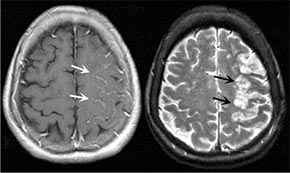

Да подобрите притока на кръв към главния мозък

При хипертония рискът от инфаркт и инсулт се повишава от високата температура на въздуха!

«При хипертония повишената температура на въздуха води до сериозно натоварване на сърдечно-съдовата система и смущенията във всички системи на организма. Кръвоносните съдове се претоварват, кръвното налягане се повишава, което увеличава риска от инфаркт и инсулт»

нормализира кръвното налягане, подобрява притока на кръв към главния мозък, успокоява нервната система, разширява кръвоносните съдове